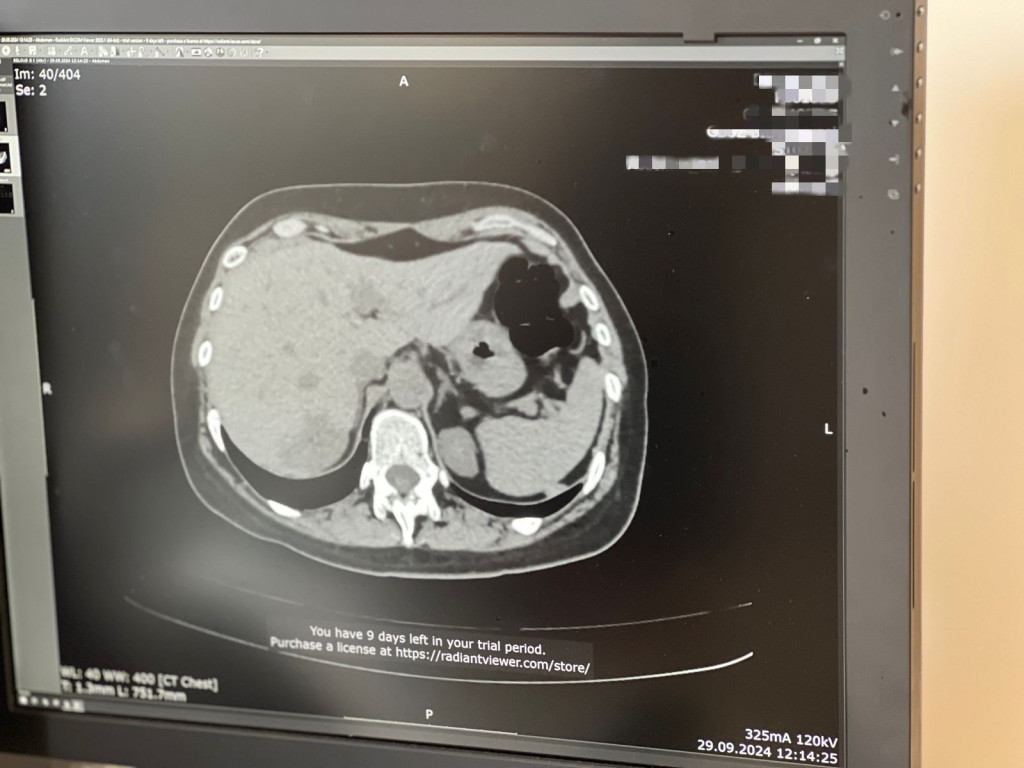

На данный момент в онкоцентре мне поручено описывать низкодозовые компьютерные томограммы. Это скрининг на раннее выявление онкопроцесса в области грудной клетки. Категория пациентов, которые входят в этот скрининг, это люди от 55 до 75 лет, обязательно курящие. Мы выявляем проблемы в легочной ткани, захватывается еще и немалая область поддиафрагматная, верхний этаж брюшной полости, где вполне возможно рассмотреть надпочечники, печень, почки. Поджелудочная железа часто попадает в зону сканирования костной структуры.